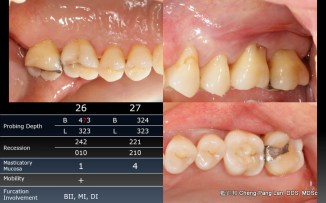

老師常常暗示著大家,implant與natural teeth之間,留下natural teeth比較好。這個我真的相信,在牙周病科的每一位學弟妹也都相信,甚至我相信週六在場的牙周病醫師都認同,但是大家有沒有想過,每隔週三一起開會的Prosthodontist、 Orthodontist都相信嗎?甚至,從實習醫師畢業就進入職場服務病人的學弟妹們,都相信嗎?